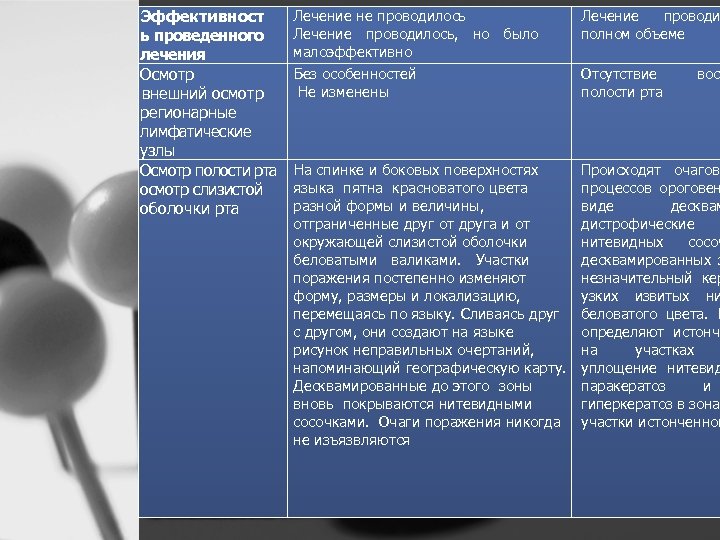

Эффективност ь проведенного лечения Осмотр внешний осмотр регионарные лимфатические узлы Осмотр полости рта осмотр слизистой оболочки рта Лечение не проводилось Лечение проводилось, но было малоэффективно Без особенностей Не изменены Лечение проводи полном объеме На спинке и боковых поверхностях языка пятна красноватого цвета разной формы и величины, отграниченные друг от друга и от окружающей слизистой оболочки беловатыми валиками. Участки поражения постепенно изменяют форму, размеры и локализацию, перемещаясь по языку. Сливаясь друг с другом, они создают на языке рисунок неправильных очертаний, напоминающий географическую карту. Десквамированные до этого зоны вновь покрываются нитевидными сосочками. Очаги поражения никогда не изъязвляются Происходят очагово процессов ороговен виде десквам дистрофические нитевидных сосоч десквамированных з незначительный кер узких извитых ни беловатого цвета. Г определяют истонче на участках уплощение нитевид паракератоз и гиперкератоз в зонах участки истонченног Отсутствие полости рта восп